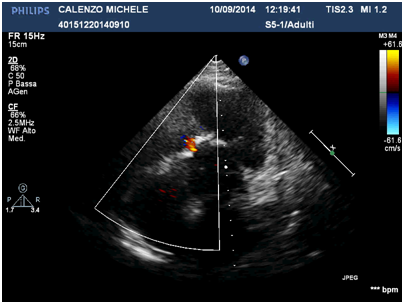

Residual mild VSD.

No residual RVOT obstruction.

Echocardiography

- Residual mild VSD.

- No residual right outflow tract obstruction.

- Good biventricular size and function.

- Slight biatrial dilatation.